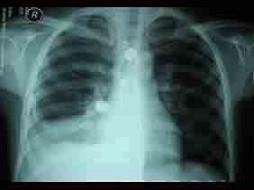

问题 6岁小儿,发热10天,伴右侧胸痛,刺激性咳嗽。查体:精神尚可,体温38.5℃,呼吸35次/min。右下肺叩诊浊音,听诊呼吸音明显减弱。胸片示右肺中部云雾状浸润影,右肺下部均匀致密阴影,肋膈角消失。血白细胞8×10/L,中性粒细胞52%,淋巴细胞48%,血沉45mm。结核菌素试验1:2000,硬结10mm×10mm,血冷凝集试验1:128。最可能的诊断是 ( )

选项 A、腺病毒性肺炎并发渗出性胸膜炎 B、支原体肺炎并发渗出性胸膜炎 C、大叶性肺炎并发脓胸 D、结核性胸膜炎 E、金黄色葡萄球菌肺炎并发脓胸

答案 B